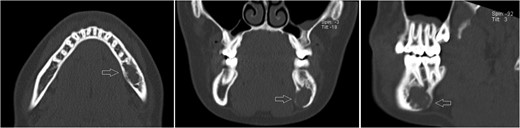

Likewise to panoramic X-ray, follow-up CT after 12 months showing no significant progression of the lesion.